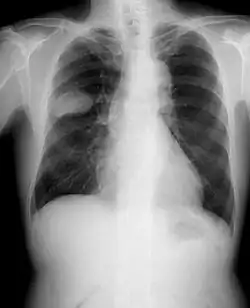

Chest X-rays are typically the first step to evaluate someone for any type of lung cancer. If images show suspicious spots on the patient's lung, a healthcare provider may order chest CT, PET, needle biopsy or bronchoscopy for further check.[33]